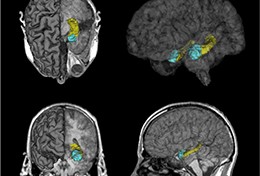

Brain pictures show the hippocampus in yellow and the amygdala in blue.

People whose blood sugar is in the high end of the normal range may be at greater risk of brain shrinkage that occurs with ageing and diseases such as dementia, according to an academic from The Australian National University. Nicolas Cherbuin, from the Centre on Ageing, Health, and Wellbeing in the ANU College of Medicine, Biology and Environment, studied 249 people aged 60 to 64 who had blood sugar in the normal range. The participants had brain scans at the start of the study and again, on average, four years later. "Numerous studies have shown a link between type 2 diabetes and brain shrinkage and dementia, but we haven't known much about whether people without diabetes with blood sugar on the high end of normal experience these same effects," said Cherbuin. "Blood glucose levels are measured in millimoles per litre (mmol/l), a normal blood glucose level is considered to be between 4.0 and 6.1 mmol/l. Those with higher blood sugar levels within the normal range were more likely to have a loss of brain volume in the areas of the hippocampus and the amygdala - areas that are involved in memory and cognitive skills - than those with lower blood sugar levels." After controlling for age, high blood pressure, smoking, alcohol use and other factors, the researchers found that blood sugar on the high end of normal accounted for six to 10 per cent of the brain shrinkage. "These findings suggest that even for people who do not have diabetes, higher blood sugar levels could have an impact on brain health," Cherbuin said.